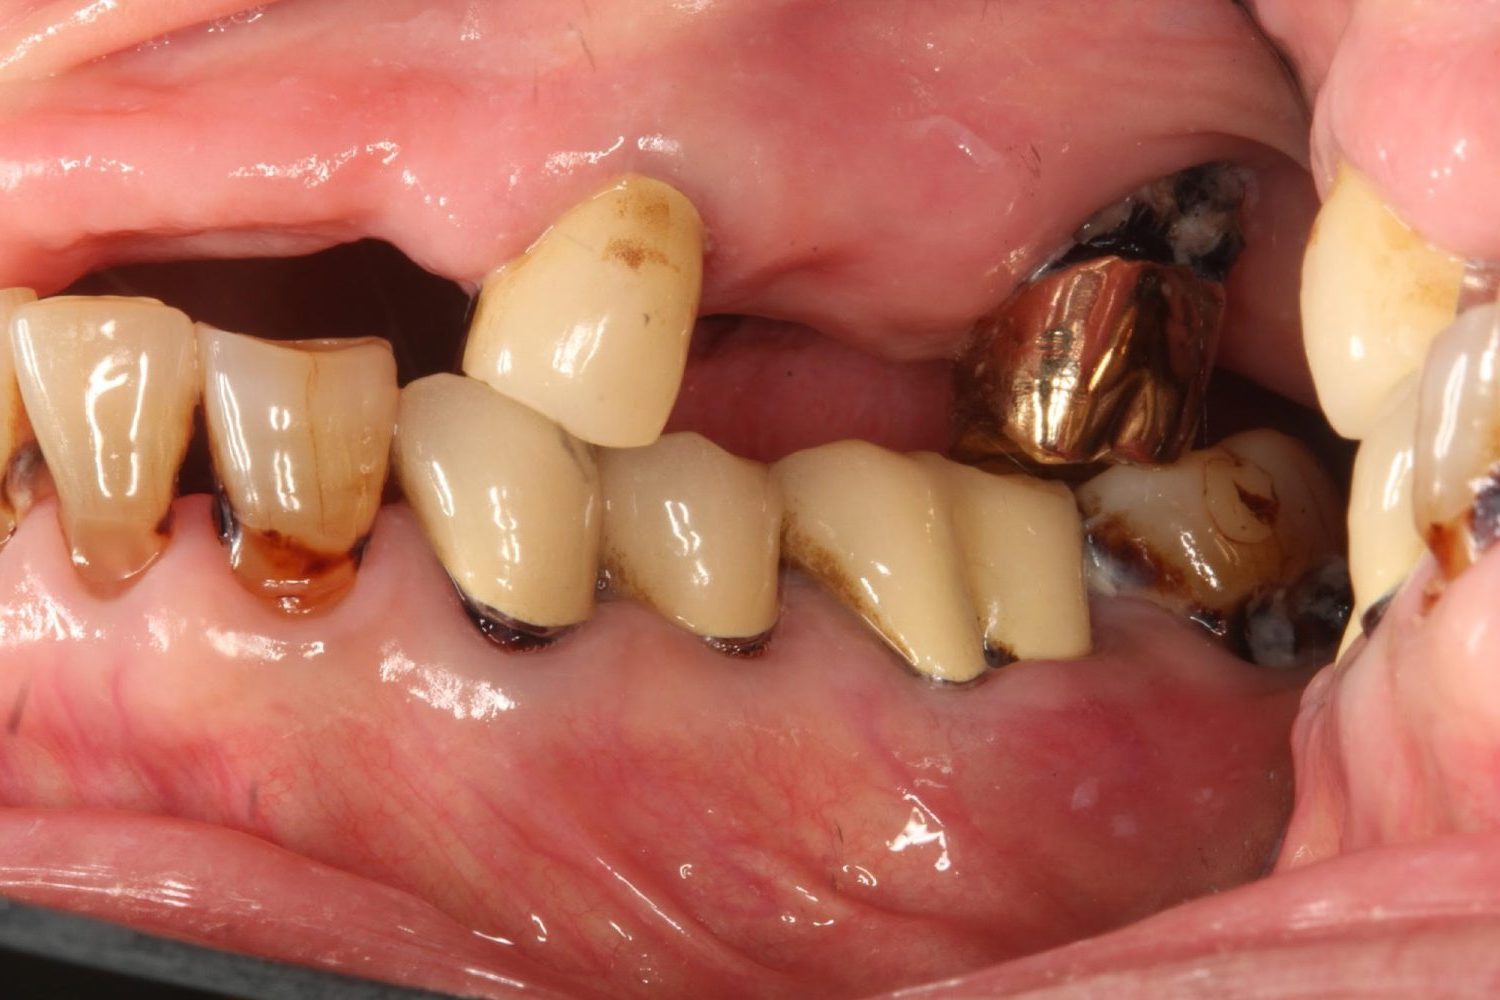

インプラント治療の症例紹介⑤

Before

After

主訴

歯肉腫脹、咬めるようにしたい

治療内容

重度歯周病により全ての残存歯保存不可能な状態。上下顎ボーンアンカードブリッジによる咬合再構成。

治療費

12,621,400円(税込)

治療期間

22ヶ月

通院回数

28回

想定されたリスク

※上部構造の形態が複雑になるため清掃が難しくなる、インプラント周囲炎の恐れがありました。

上顎8本下顎7本のインプラント体埋入によるボーンアンカードブリッジ。